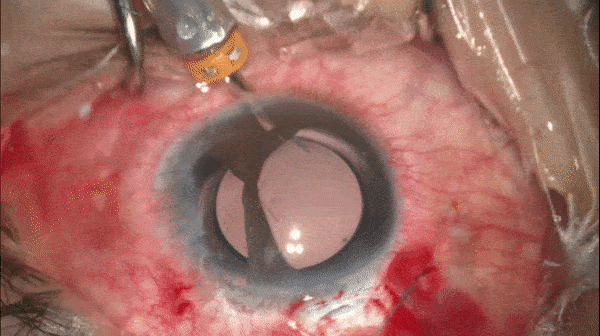

牵拉虹膜使粘连的虹膜松解,瞳孔成形。

开睑器怎么用术说睛彩 | 金海鹰教授:使用8-0缝线的无巩膜瓣人工晶体固定手术_https://www.jmylbn.com_新闻资讯_第24张